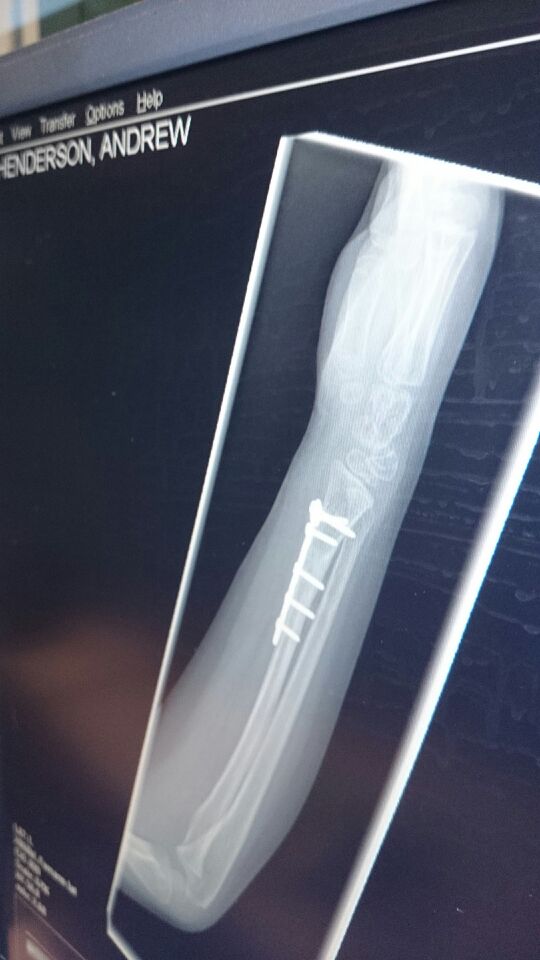

My sons broken arm and 4 surgeries